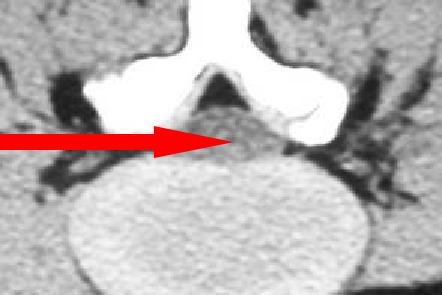

• 行腰椎CT和MR检查,观察腰椎问盘突出部位和程度、是否伴有腰椎管狭窄和椎间盘钙化,确定手术方式、工作通道的置入位置与方向。

三、术前设计仔细复习患者的腰椎MRI、CT及CR片,确定穿刺位置,尤其是存在移行椎。四、定位针位置TOMShidi针的定位决定手术成功与否的关键。